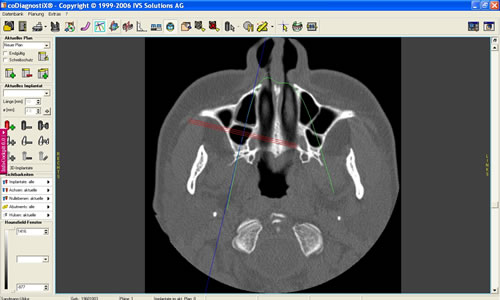

Mit der Entwicklung der Computertomographie (CT) und in jüngerer Vergangenheit der digitalen Volumentomographie (DVT) stehen Untersuchungsverfahren zur Verfügung, mit denen sehr viel einfacher und genauer das Knochenangebot vermessen werden kann. Von dem Patienten wird in einer Klinik oder Praxis, die über die entsprechenden Möglichkeiten verfügt, ein Spezialröntgenbild (DVT/CT) des Ober-, seltener des Unterkiefers, angefertigt. Dieses spezielle Röntgenbild dauert für einen Kiefer 20 Sekunden. Der große Vorteil liegt darin, dass der gesamte Kiefer durch den Computer in über 100 Schnitten abgebildet werden kann. Auf diesen Schnittbildern können Höhe und Breite des Knochens direkt abgemessen werden (Abb. 5.5).

Nach dem Überspielen der Daten auf den Praxiscomputer des Zahnarztes eröffnen sich weitere Möglichkeiten. Der Kiefer wird in verschiedenen Ebenen gleichzeitig dargestellt und damit eine räumliche Auswertung möglich. Neben der Vermessung des Kiefers kann die Knochenqualität durch Dichtemessungen beurteilt werden. Damit lässt sich z.B. eine bestimmte Knochenerkrankung, die Osteoporose, nachweisen bzw. ausschließen.

Am Praxiscomputer lassen sich Besonderheiten des jeweiligen Patienten herausarbeiten, wie z. B. die Beschaffenheit der Nasennebenhöhle. Hier können verschiedenen Knochenleisten (Abb. 5.6) oder Schleimhautveränderungen das Implantieren erschweren. Umso wichtiger ist es durch ein Computertomogramm diese Variationen vor der Implantation zu kennen. In den speziellen Programmen können bereits Implantationen simuliert werden (Abb. 5.7, 5.8).

Abb. 5.7: Implantations- simulation am PC.

Abb. 5.8: Implantatplanung.

Dabei werden das Implantat, die richtige Länge und der geeignete Durchmesser ausgewählt. Entscheidend ist auch die Richtung, in der implantiert werden muss. Auch dies lässt sich bereits am Computer auf den Schnittbildern simulieren. Eine dreidimensionale Darstellung des Knochens und die Möglichkeit das äußere Profil zu zeigen, verdeutlichen den späteren Sitz der Implantate und die Beziehung zum Gegenkiefer, zur Kauebene, zu Wangen und Lippen lassen die spätere Versorgung kosmetisch vorhersehen (Abb. 5.9, 5.10). Eine Dichtemessung um die Implantate schließt die Planung ab.

Mit diesem Untersuchungsverfahren ist die Implantation auch bei schwierigen Situationen möglich und sehr sicher geworden.

Im Oberkiefer wird diese Untersuchung und Planung in unserer eigenen Praxis seit Jahren routinemäßig durchgeführt. Die erheblich verbesserten Ergebnisse rechtfertigen den Mehraufwand, die geringfügig höhere Strahlenbelastung der heutzutage modernen Geräte sowie die Kosten, die dadurch entstehen.